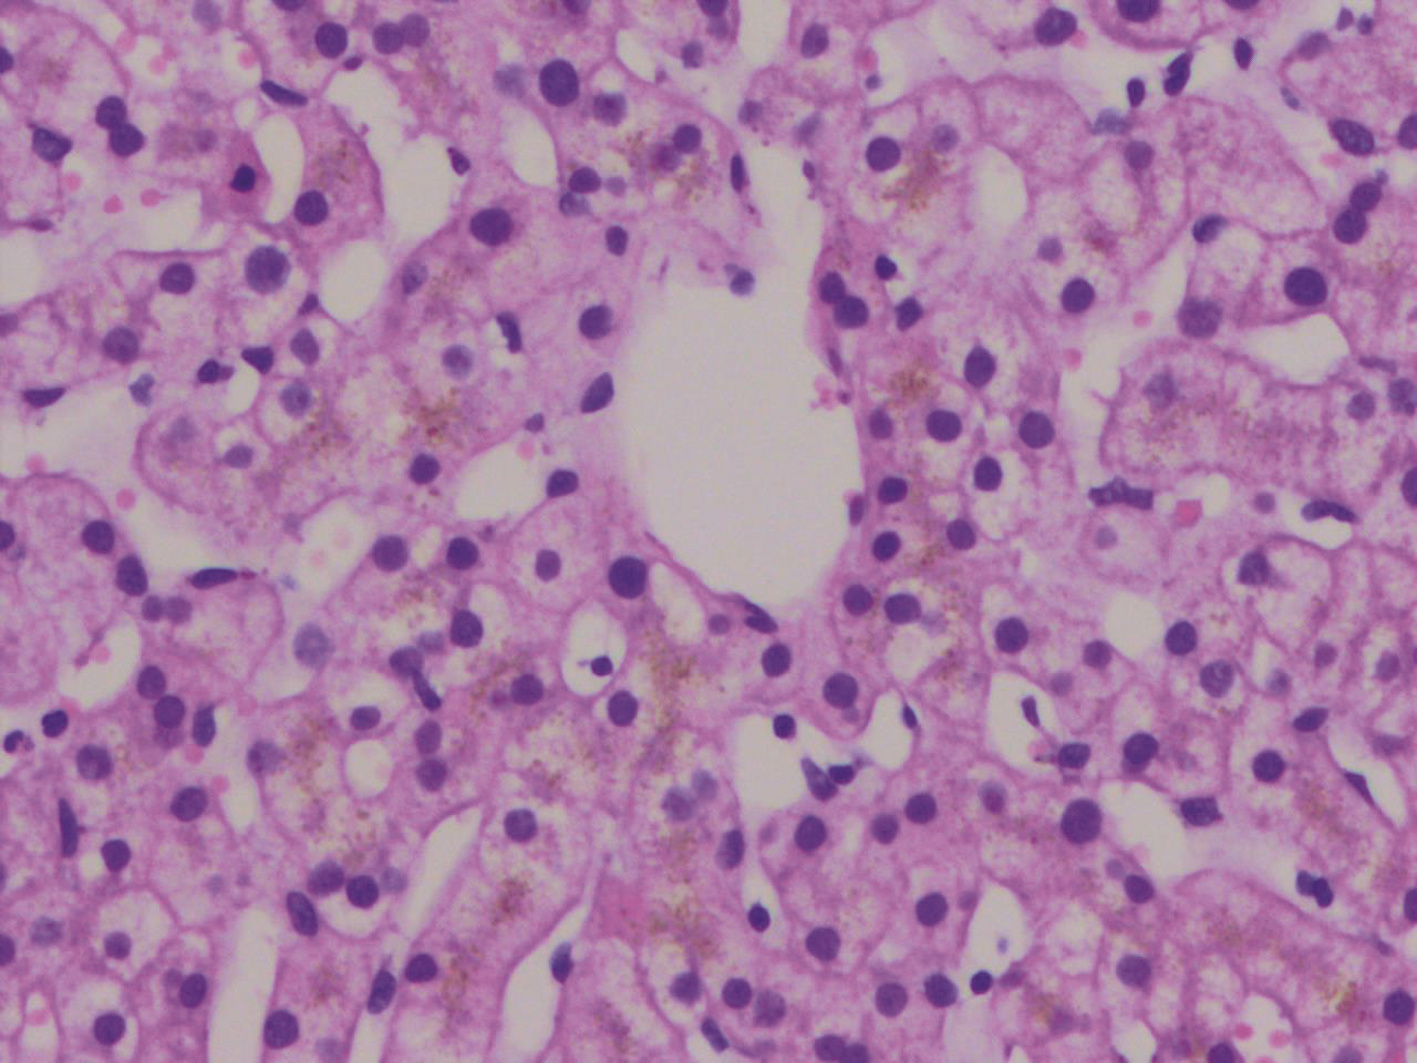

Objective  To investigate the effect of Yipi Yanggan prescription on the malignant transformation of liver stem cells in liver precancerous lesion induced by diethylnitrosamine (DEN) and its possible molecular mechanism.  Methods  A total of 35 male Sprague-Dawley rats were randomly divided into normal control group (blank group), DEN model group (model group), DEN+Yipi Yanggan prescription group (Yipi Yanggan prescription group), and DEN+Hugan tablet group (Hugan tablet group), with 5 rats in the blank group and 10 rats in the other three groups. Intraperitoneal injection of DEN was performed to establish a model of liver precancerous lesion, the rats were sacrificed after 16 weeks of administration. The serum levels of alanine aminotransferase (ALT), aspartate aminotransferase (AST), and albumin (Alb) were measured; liver tissue was collected to observe the changes in size and appearance and calculate liver weight ratio (liver index); HE staining and Sirius Red staining were used to observe the pathological and morphological changes of rat liver tissue; immunohistochemistry was used to measure the expression of OV6 and glutathione S-transferase-Pi (GST-Pi); RT-PCR was used to measure the mRNA expression of EpCAM, CD133, and CD90, and Western blot was used to measure the protein expression of PI3K, Akt, and mTOR and their phosphorylation level. A one-way analysis of variance was used for comparison between multiple groups, and the least significant difference t-test was used for further comparison between two groups.  Results  Compared with the model group, the Yipi Yanggan prescription group and the Hugan tablet group had significant improvements in liver pathology and morphology, significant reductions in liver index and the levels of ALT and AST, and a significant increase in the level of Alb (all P < 0.05), as well as significant reductions in the protein expression levels of GST-Pi, OV6, p-PI3K, p-Akt, and p-mTOR and the mRNA expression levels of EpCAM, CD133, and CD90 (all P < 0.05). Compared with the Hugan tablet group, the Yipi Yanggan prescription group showed a more significant protective effect on the liver, with significant reductions in liver index and the levels of ALT and AST, and a significant increase in the level of Alb (all P < 0.05), as well as significant reductions in the protein expression levels of GST-Pi, OV6, p-PI3K, p-Akt, and p-mTOR and the mRNA expression levels of EpCAM, CD133, and CD90 (all P < 0.05).  Conclusion  Yipi Yanggan prescription can improve liver precancerous lesion induced by DEN in rats by inhibiting the malignant transformation of liver stem cells, and its mechanism of action may be associated with the PI3K/Akt/mTOR signaling pathway.

Effect of Yipi Yanggan prescription on malignant transformation of liver stem cells in rats with liver precancerous lesion and its mechanism of action

Di JU, Mi LI, Man HAN, Bingying FANG, Shuguang YAN, Jingtao LI

2022, 38(4): 865-871. DOI: 10.3969/j.issn.1001-5256.2022.04.023

Abstract(1711) HTML (530) PDF (3795KB)(78)

Abstract: